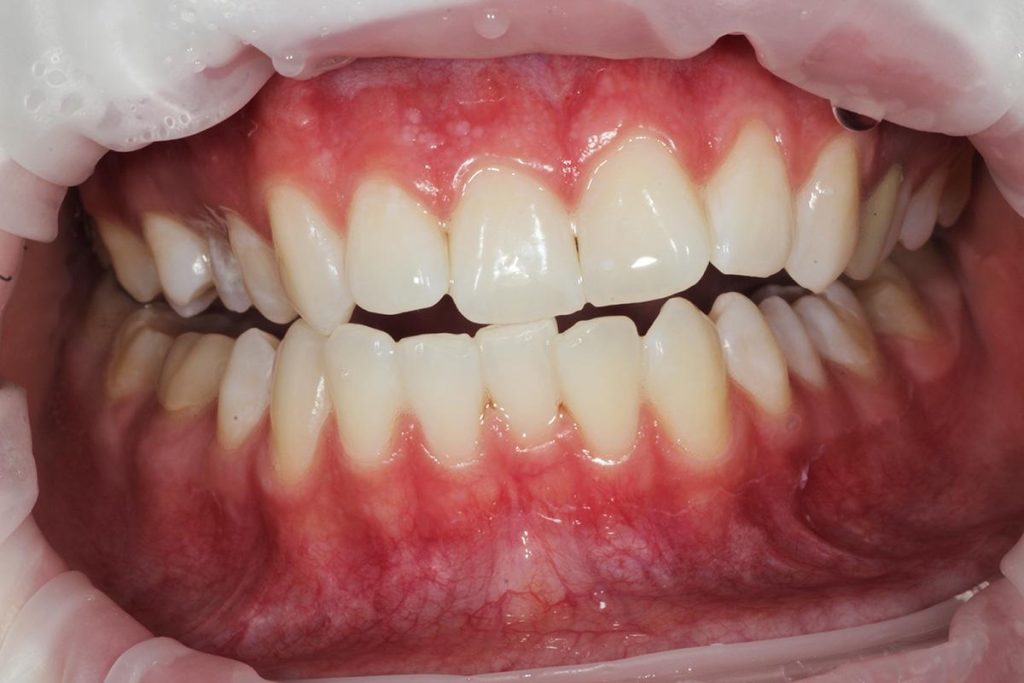

Dzięki precyzyjnej diagnostyce, doktor Magdalena Zawirska opracowała kompleksowy plan leczenia, który obejmował: stomatologię zachowawczą, periodontologię i protetykę stomatologiczną. Zastosowano licówki i korony pełnoceramiczne, przeprowadzając kompleksową rekonstrukcję zwarcia.

Pacjentka może się teraz cieszyć się pięknym i zdrowym uśmiechem